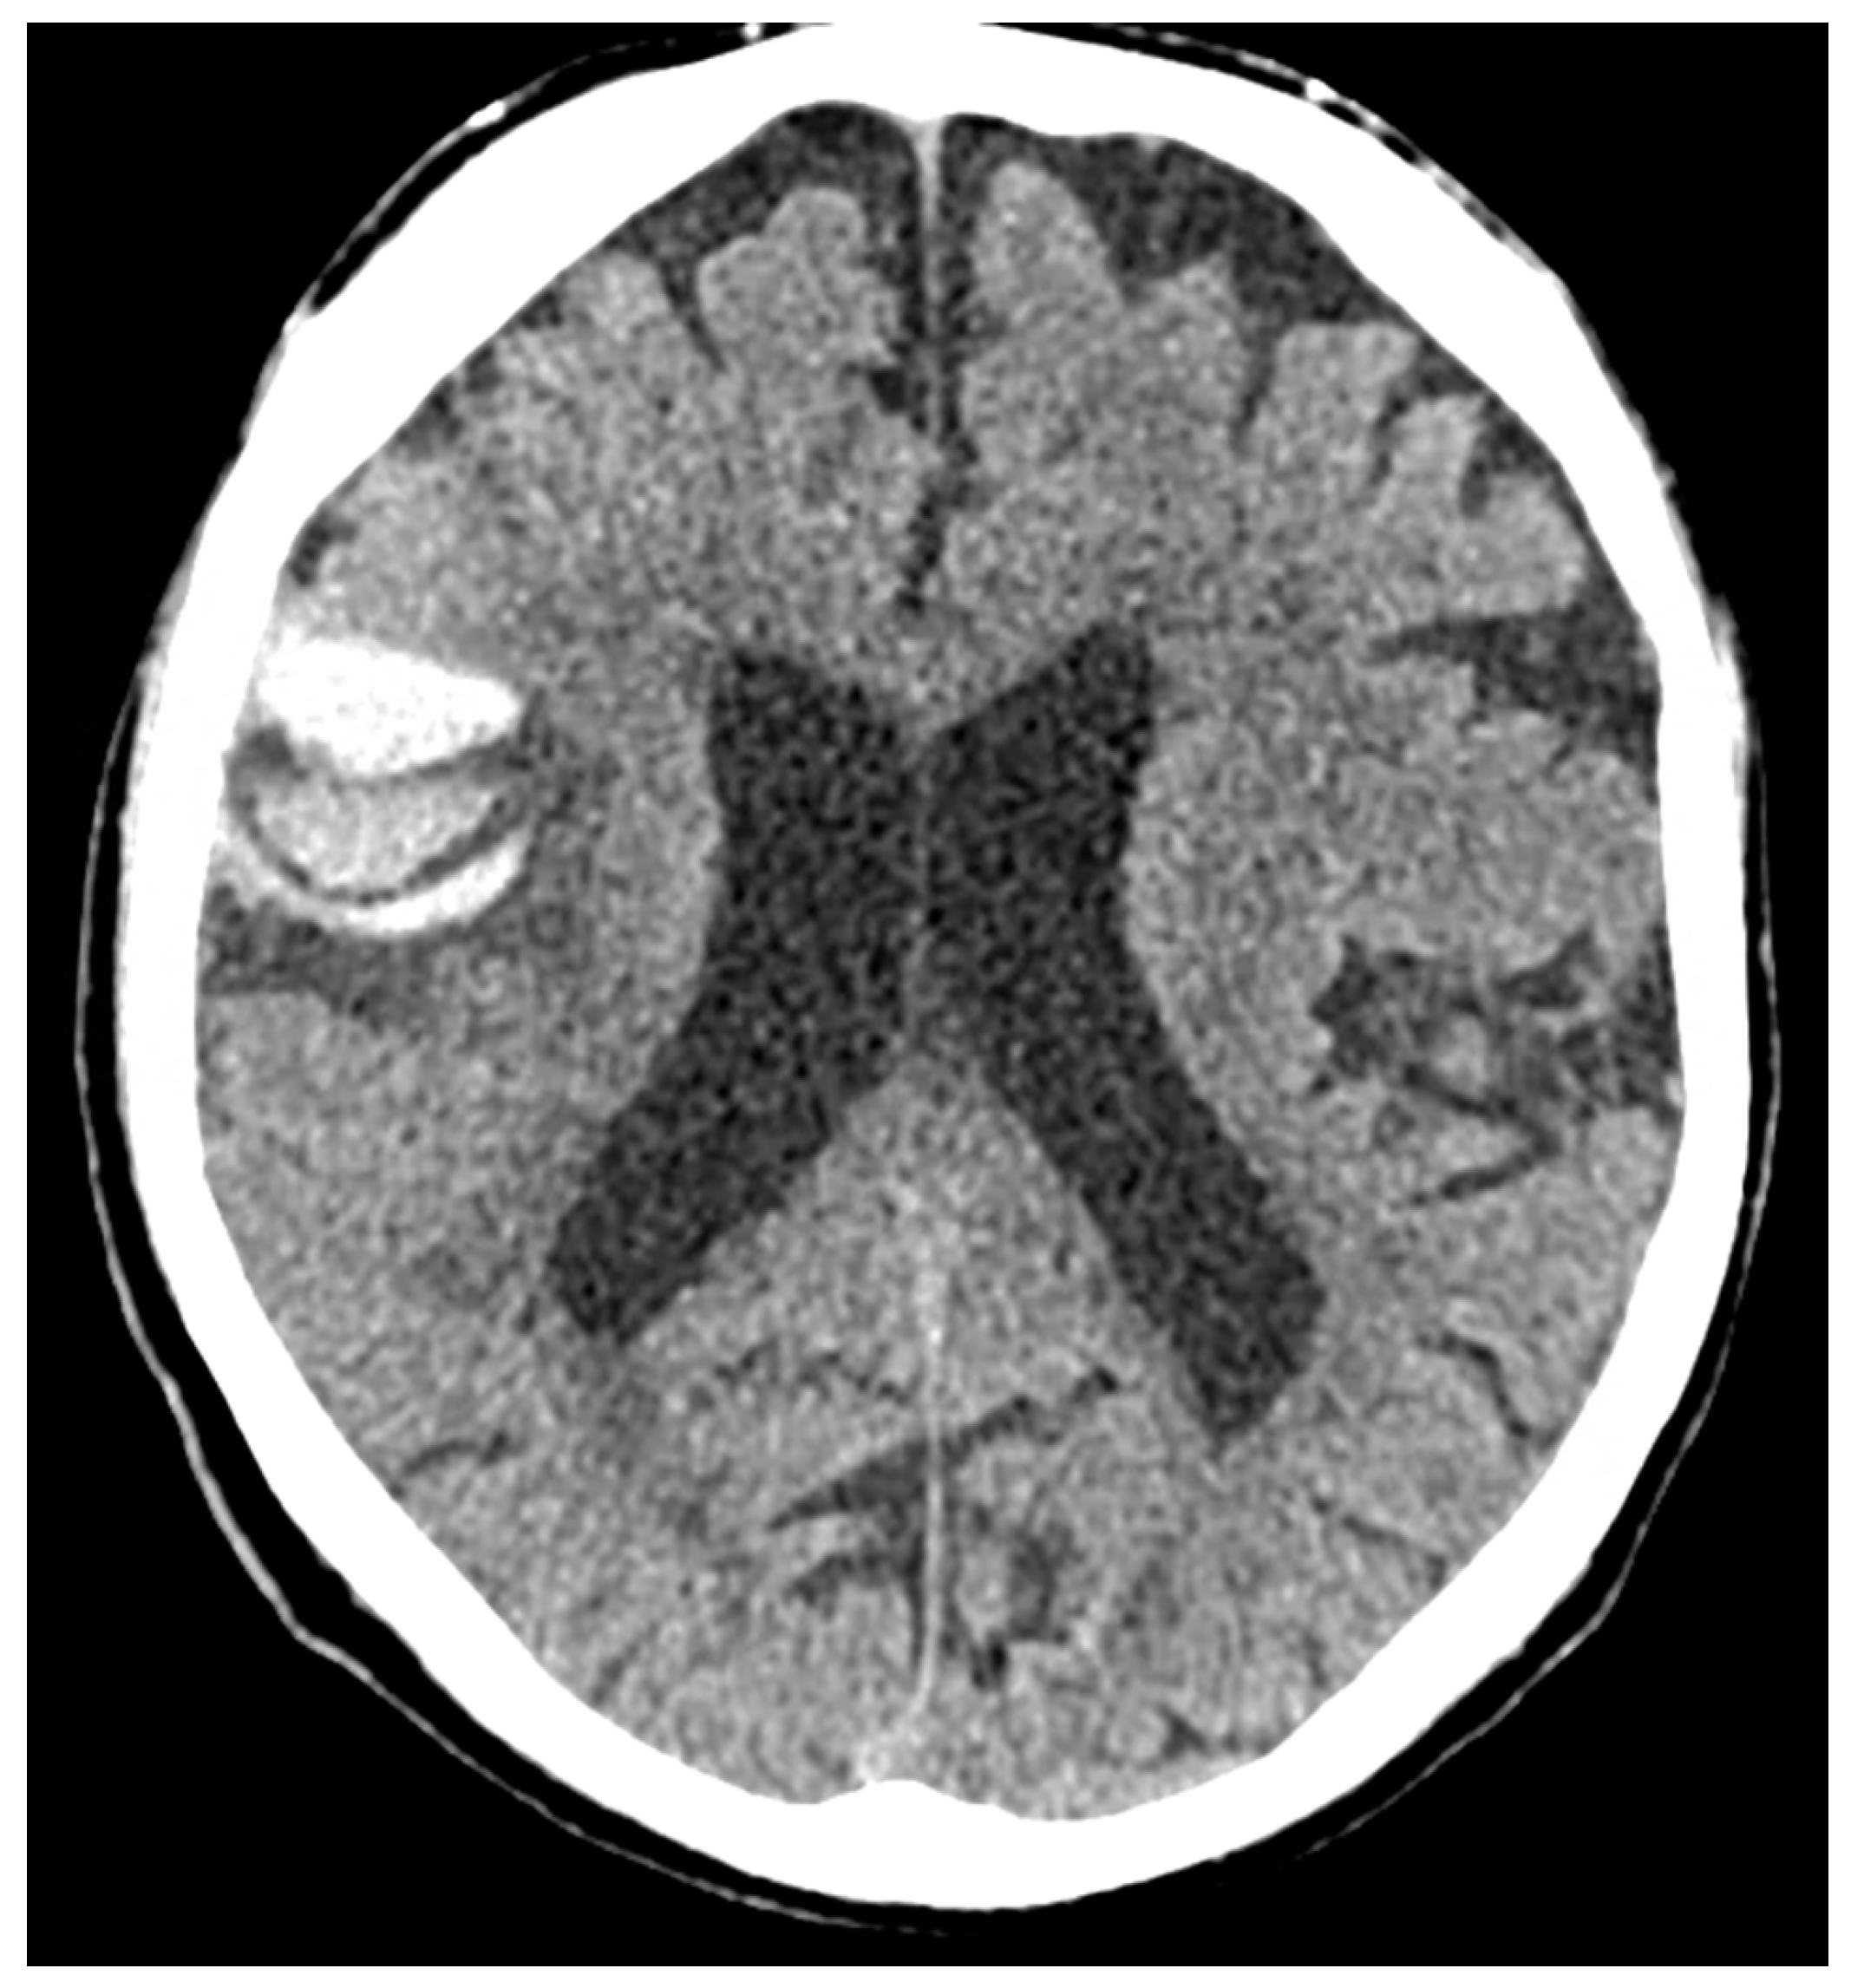

7. Structural Neuroimaging Markers